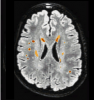

Wisconsin White Matter Hyperintensities Segmentation Toolbox

Ithapu, V., Singh, V., Lindner, C., Austin, B. P., Hinrichs, C., Carlsson, C. M., Bendlin, B. B. and Johnson, S. C. (2014), Extracting and summarizing white matter hyperintensities using supervised segmentation methods in Alzheimer's disease risk and aging studies. Hum. Brain Mapp.. doi: 10.1002/hbm.22472